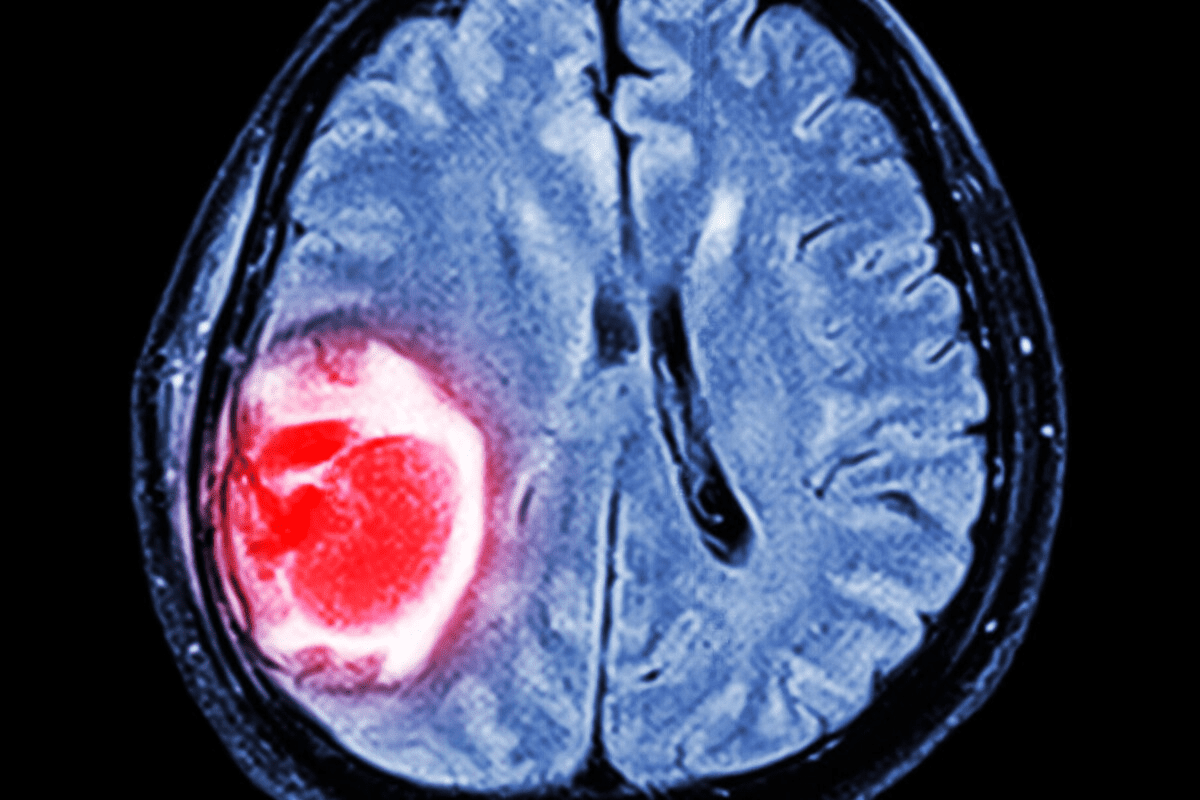

Imaging Tests

Imaging tests are key to confirming spinal stenosis. They show detailed images of the spine. This helps doctors spot narrowing and compression areas.

Common imaging tests used include:

- X-rays: Provide initial images of the spine’s structure

- MRI (Magnetic Resonance Imaging): Offers detailed images of soft tissues, nerves, and the spinal cord

- CT (Computed Tomography) scans: Provides detailed images of the spine’s bony structures